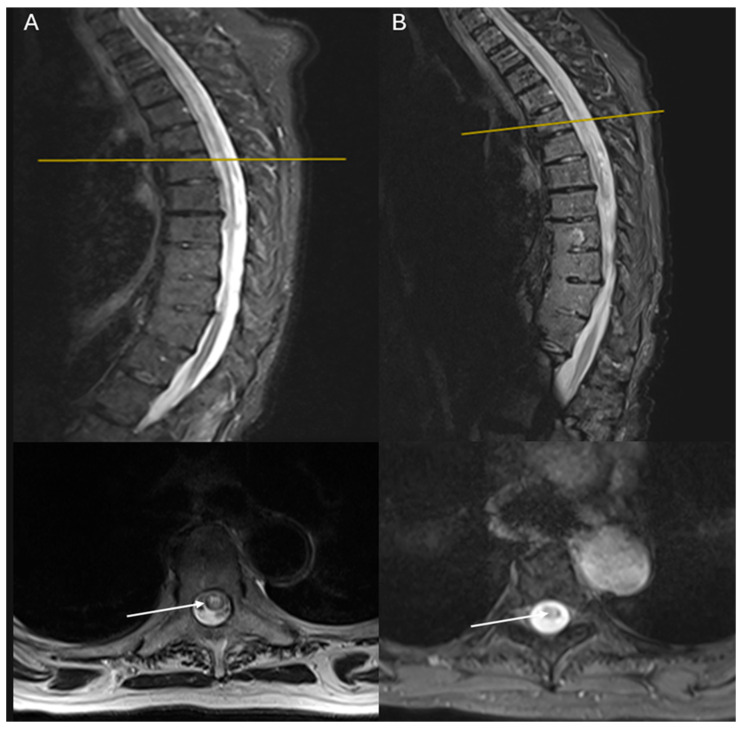

背景和临床意义:视神经脊髓炎(NMO)是中枢神经系统(CNS)的一种慢性脱髓鞘炎症性疾病,由抗水通道蛋白-4 (AQ4)受体的自身抗体介导。在NMO谱系中,其他自身免疫性疾病也共存,尽管它们与系统性红斑狼疮(SLE)的关联很少见。病例介绍:我们报告两例70多岁的患者,在SLE的背景下被诊断为NMO。第一个病例涉及一位78岁的女性,患有药物性SLE和胸椎脊髓炎,她在三周内发展为t4级不完全截瘫。第二个病例涉及一名71岁的女性,有SLE和重症肌无力病史,表现为宫颈脊髓炎,行走能力进行性恶化和c4级麻痹超过两个月。两例患者均检测到血清抗aq4滴度升高,确定了NMO的诊断,并与非典型的slel相关性脊髓炎进行了区分。两例患者均给予高剂量静脉注射皮质类固醇并逐渐减量,同时给予环磷酰胺,随后给予利妥昔单抗。第一个病人的反应很差,而第二个病人的反应有所改善。结论:NMO与SLE共存的情况很少见,但结缔组织疾病患者出现脊髓炎应引起对NMO的怀疑,特别是在老年女性和SLE诊断后几年。治疗时间至关重要,因为治疗NMO的延误可能导致累积和致残损害。

Background and Clinical Significance: Neuromyelitis optica (NMO) is a chronic demyelinating inflammatory disease of the central nervous system (CNS), mediated by autoantibodies against aquaporin-4 (AQ4) receptors. In the spectrum of NMO, other autoimmune diseases also coexist, though their association with systemic lupus erythematosus (SLE) is rare. Case Presentation: We present two cases of patients in their 70s who were diagnosed with NMO in the context of SLE. The first case concerns a 78-year-old woman with drug-induced SLE and thoracic myelitis who developed T4-level incomplete paraplegia over three weeks. The second case involves a 71-year-old woman with a history of SLE and myasthenia gravis, presenting with cervical myelitis with progressive worsening of walking and C4-level paraparesis over two months. In both cases, elevated serum anti-AQ4 titers were detected, establishing the diagnosis of NMO and differentiation from an atypical manifestation of SLE-related myelitis. High doses of intravenous corticosteroids with gradual tapering, along with cyclophosphamide, followed by rituximab, were administered in both patients. The first patient showed a poor response, while the second showed improvement. Conclusions: The coexistence of NMO with SLE is rare, but the occurrence of myelitis in patients with connective tissue diseases should raise the suspicion of NMO, especially in elderly women and several years after the diagnosis of SLE. Time to treatment is critical, as delays in treating NMO can result in cumulative and disabling damage.